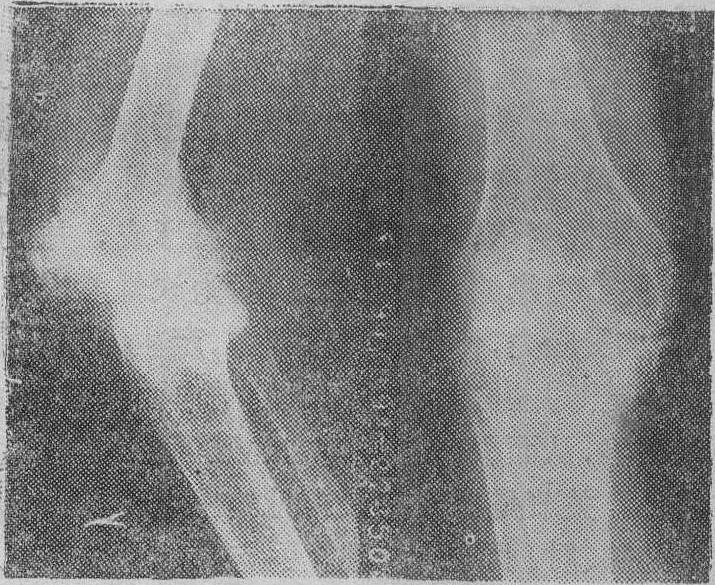

膝关节血友病性关节病

表现为关节间隙狭窄、破坏,骨质疏松,并有骨赘形成